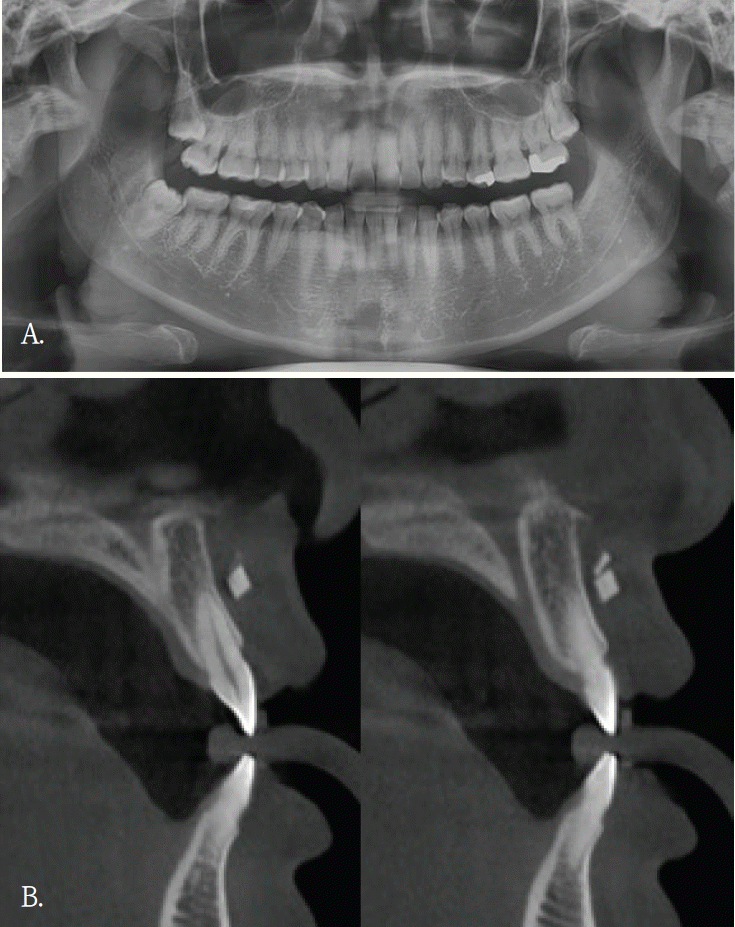

Fig. 5.

A. Panoramic radiograph. An extraction socket of the left maxillary first molar is noted. Diffuse haziness of the left maxillary sinus is observed; no other definite abnormality is identified. B. Panoramic reconstruction, C. cross-sectional cone-beam computed tomographic images. Soft-tissue density nearly fills the left maxillary sinus. A small radiopaque foreign body is identified at the floor of the sinus.

임플란트 식립 중 식립체가 시야에서 소실되어 위치 확인을 위해 60대 여자환자에서 파노라마방사선검사를 시행하였다. 파노라마방사선영상에서 임플란트 식립체로 추정되는 금속성 방사선불투과성 구조물이 우측 비강 부위에 중첩되어 관찰되었고 영상에서 비강 하연 부근에 위치한 것처럼 보였다(Fig. 4A). 이에 비강 및 상악 치조골과의 정확한 위치 관계를 평가하기 위해 콘빔CT 검사를 시행하였다. 콘빔CT에서 해당 구조물은 고음영 금속성 구조물로 확인되었으며, 상악 우측 전치부 측와 부위의 순측 연조직에서 관찰되었다(Figs. 4B and C). 또한 비강저 및 상악 치조골 피질골의 연속성이 보존되어 구조 발치와가 관찰되었다(Fig. 5A). 이러한 소견은 좌측 상악동 점막의 염증성 변화 가능성을 시사하였다. 상악동 병변의 범위 및 발치와와 상악동하연의 관계를 평가하기 위해 콘빔CT검사를 시행하였다. 콘빔CT에서 좌측 상악동 내에 연조직음영에 의한 혼탁이 관찰되었으며, 이는 상악동의 약2/3이상을 채우는 양상이었고 상악동 소공주변까지 연장되어 보였다. 또한, 상악동 전하방에서 경계가 명확한 작은 타원형의 균질한 고음영 구조물이 관찰되었으며, 골밀도에 해당하는 방사선불투과성 이물질로 판단되었다(Figs. 5B and C). 해당 고음영 소견은 파노라마방사선영상에서는 명확히 구분되지 않았다. 환자의 발치 병력을 고려할 때 해당 구조물은 상악동 내로 이동한 잔존치근이 의심되었으며, 외과적 제거를 시행하였다. 제거된 이물질은 상악동 내 잔존 치근으로 확인되었다.

콘빔CT는 해부학적 구조물이나 이물질 위치를 확인하고, 인접 구조물과의 관계를 파악하는데 유리하다. 2차원 영상에서 발생되는 중첩을 줄이고, 3차원적인 위치정보를 제공함으로써 치과 임플란트 치료계획이나 치아 교정 진단과정에서 필수적인 영상검사이다. 또한, 임플란트 식립이나 매복치 발거등 외과적 치료과정에서도 진입 경로 결정에 도움을 주어 술 후 합병증을 감소시킨다.콘빔CT의 원래 촬영 목적과는 관계없이, 우연히 발견되는 소견들이 있다. 이러한 소견의 빈도는 24.6~94.3%로 보고마다 매우 다양하다[1,2]. 소아 및 청소년연령군에서의 빈도도 0.4~80.3%로 다양하지만 매우 자주 발견된다[3]. 발견되는 부위는 치아 및 치조골을 벗어난 부위가 대부분으로 주로 부비동 및 비강, 혈관, 연조직, 경추이다[1-3]. 그러므로, 콘빔CT 검사할 때 촬영목적 부위 뿐 만 아니라 그 외 다른 부위의 판독도 충분히 이루어져야 한다[2,4,8]. 특히 어린 환자에서는 방사선방어를 고려하여, 관심부위 뿐 만 아니라 콘빔CT영상에 포함된 모든 부위에서 영상판독이 충분히 이루어져야 한다[3]. 우연히 발견되는 소견의 양상도 매우 다양하다. 부비동 및 비강에서는 점막비후, 점액저류낭, 비중격만곡이 많이 발견되고, 혈관부위에서는 경동맥석회화가 주로 발견된다. 연조직에서는 편도석, 경동설골인대골화가 주로 발견되는 소견이다[1-3]. 대부분 해부학적 변이이거나 의학적 조치가 필요하지 않은 경우이다.하지만 추적검사나 치료가 필요한 임상적으로 의미가 있는 소견들도 매우 다양한 빈도로 발견된다. 최소 0.4%에서 최대 37%까지로 전체의 약 1/6-1/3 정도에서 발견되어 주의깊은 콘빔CT 영상판독이 필요하다. 이들 소견중에는 치근단병소, 치성낭, 종양도 있었으며[1-3], 오랜 기간 동안 인지하지 못했던 이물질도 발견된다[1,4,6,8].우연히 발견된 이물질들은 치조골 및 악골 부위가 아닌 다른 부위에서 많이 관찰되었다. 교정목적으로 촬영된 콘빔CT에서 비강내에 플라스틱 이물질이 우연히 발견되어 이비인후과 의뢰 후 이물질을 제거한 증례보고가 있다[4]. 증상이 없어서 이물질의 유무를 알 수 없었지만, 콘빔CT에서 비강내 이물질이 확인되어 외과적으로 제거한 증례보고도 있다[5,6]. 증상이 있어 촬영한 상악 견치 치근단방사선사진에서 모호한 방사선불투과성 이물질이 관찰되어, 이후 촬영한 콘빔CT에서 이물질이 유리조각으로 확인된 증례보고도 있다[8]. 이 증례는 유리같은 이물질은 치근단이나 파노라마방사선사진에서는 명확하게 관찰되지 않았기에 콘빔CT검사가 매우 유용하였던 경우이다.증례 1에서도 초진시 파노라마영상에서는 유리조각을 관찰할 수 없었기에 연조직 병변으로 진단되었으나, 재내원후 촬영된 콘빔CT영상에서 연조직내에 있었던 이물질임으로 확인된 경우이다. 윗입술에 있었던 유리조각이 방사선불투과성 물질이였지만, 상악 전치부와 중첩되어 파노라마방사선영상에서 뚜렷하게 구분되지 않았다.증례 5와 같이 파노라마방사선영상에서 모호하게 관찰되었거나 증례 3과 4같이 파노라마방사선영상에서 협-설위치를 명확하게 알 수 없었던 경우, 콘빔CT영상에서 임상적으로 의미있는 이물질임을 확인되었고 외과적 치료가 시행되었던 증례들이다. 특히, 이들 소견은 악골이 아닌 안면 연조직 부위에서 관찰되어, 주의 깊은 영상판독의 중요성을 다시금 일깨워 준다.한편, 안면미용시술을 받은 환자들이 치과에 많이 내원하면서 우연히 발견되는 이물질 소견 중 하나가 미용 필러이다[9]. 치과의사들에게 아직은 익숙하지 않은 방사선영상 소견이고 부위도 치아나 악골이 아닌 연조직부위에서 관찰되기에 영상 판독에서 배제될 가능성이 있다. 미용필러도 파노라마방사선 영상에서보다는 콘빔CT영상에서 위치나 형태, 양상을 잘 관찰할 수 있다.본 증례들은 파노라마방사선영상에서 인지되지 않았던 이물질 3증례와 파노라마방사선영상에서 의심된 이물질이 콘빔 CT에서 위치와 형태가 명확히 규명된 2증례를 포함한다. 이를 통해 악안면 콘빔CT 판독 시 촬영 목적 부위에 국한하지 않고 영상에 포함된 전체 영역을 체계적으로 검토함으로써, 이물질과 같은 우연히 발견되는 소견이 누락되는 것을 줄일 수 있음을 알았다. 또한 추가 촬영이나 불필요한 검사로 인한 방사선 노출을 예방하여, 콘빔CT 검사의 정당성과 임상적 유효성을 강화하는 뒷받침이 됨을 알았다.